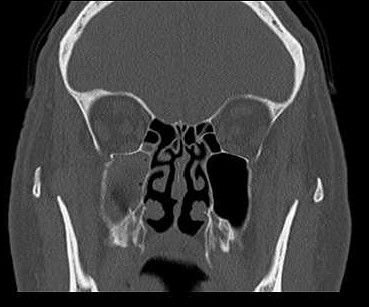

Distinguir radiográficamente un seno sano de uno enfermo no es tan problemático teniendo en cuenta su forma, que es inconsistente, con muchos lobulaciones, por lo tanto, en caso de sinusitis, se puede observar opacificación, engrosamiento de la mucosa y/o acumulación de líquido 17(Figura 3).

Diferentes estudios han demostrado que la SO podría representar entre el 45% y 75% de la opacificación unilateral del seno maxilar visibles en la TC 1,14,17.

Los estudios de SO han mostrado una extensión frecuente de la enfermedad a los senos etmoidales anteriores y frontales 13. Craig y cols.7, observaron que la extensión extramaxilar hacia los senos etmoidales y frontales se observó en la TC en casi el 70% y el 40% de los pacientes, respectivamente.

Saibene y cols.8 encontraron que el 41% de pacientes con SO tratados quirúrgicamente, tenían compromiso extramaxilar unilateral, en el 40,3% restante la afección nasosinusal se limitó al seno maxilar, y casi el 20% eran bilaterales.

En un artículo de Turfe y cols. 14, la SO se asoció con enfermedad del seno etmoidal anterior (88%) y del seno frontal (60%) en la TC, y purulencia del meato medio en la endoscopia nasal. Hubo una participación aproximadamente igual entre los lados derechos (45%) e izquierdo (55%).